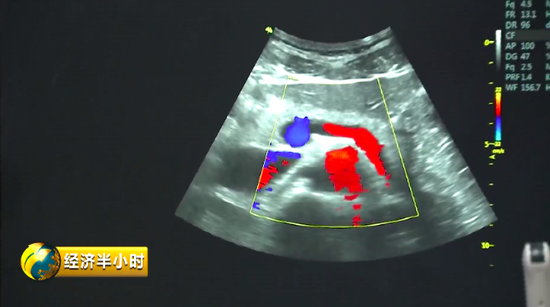

彩色B超有一个特殊的彩色B超设备,不仅能够精确诊断,还能帮助大夫有效地给予患者治疗。也就是说,在治疗疾病时,在超声波的介入下,药物被精准送达病变位置,释放药物,从而实现靶向治疗。而且这个彩色B超设备副作用很少,安全性特别好。《经济半小时》记者在苏州工业园区了解到,目前这种彩色B超设备在国际上已经达到一流水平。

研发部门显示速率越快,意味着成像效果越好,医生的诊断和治疗也会更精确。公司研发总监高文友告诉记者,他们一代数据处理平台的速度可以理解成 5G 速度的 10 倍,而目前开发出来的二代产品,传输带宽比上一代高了将近150倍;成像显示的速率,也将近快了一百倍以上。

彩色B超设备解放军总医院第一医学中心超声诊断科了解到这个产品后,没有想到国产的机器居然也有世界一流水平的产品,率先引进了八台。而国产高质量“彩超”的登台亮相也让以往那些高不可攀的国外“彩超”价格纷纷降价,原来300万左右的进口设备降到180万。